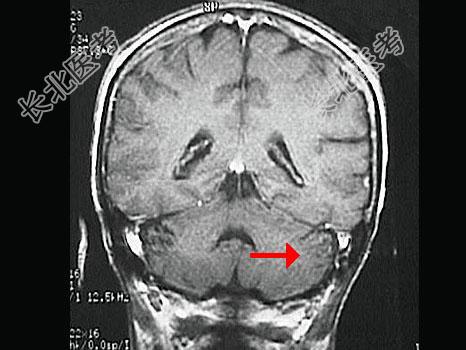

- 单项选择题如图箭头所示为颅脑哪个部位 ( )

A、顶叶

B、枕叶

C、小脑

D、脑干

E、额叶